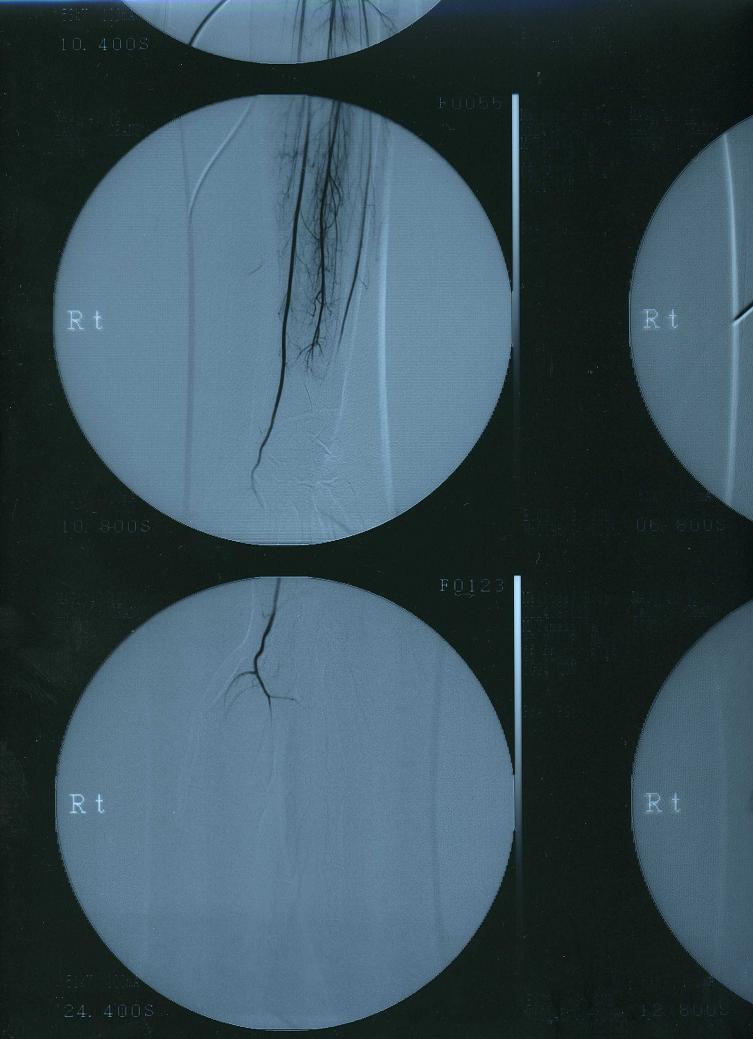

そして、初めてカミングアウトする病気は…病名『ビュルガー病』

私の場合、どうも突然変異の生まれつきだったみたい。

で、顕著に症状が酷く出たのが28歳の時…

この病気は9割方、男性がかかる病気なので、女性と老人が疑わしい時は男性より厳しい検査をします。

その検査を見事パスしてしまった時は1ヶ月ぐらいずっと泣いたっけ…

薬と冬場の血管拡張の点滴でなんとか現状維持してるんだけど…

血液が指の先に十分に流れないので…